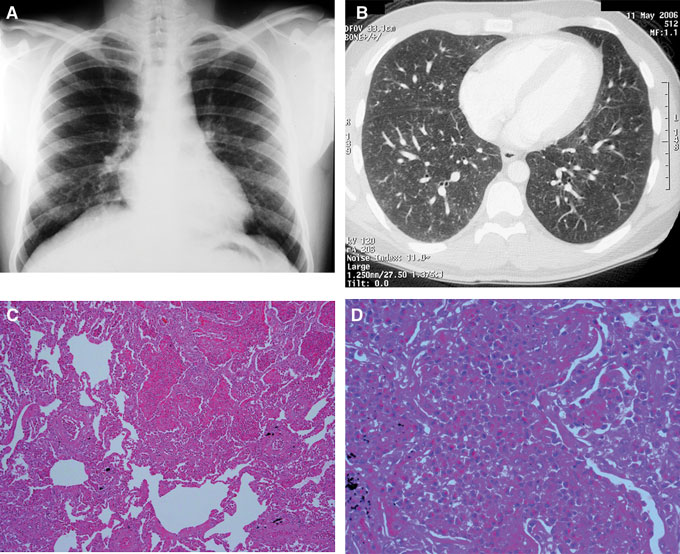

A 27-year-old man presented to an infectious diseases outpatient clinic in May 2006 with a 3-month history of nocturnal dry cough, paroxysmal dyspnoea, malaise and unintentional weight loss of 5 kg. He had previously presented to a general practitioner and was treated with two courses of antibacterial drugs without a decrease in symptoms. He had no significant past history of chronic respiratory illness or tuberculosis, was a non-smoker and had been working in Australia for 5 years. He was born in India and had recently returned there on a holiday to visit family and friends. Physical examination, including respiratory system examination, was unremarkable. Full blood examination revealed marked eosinophilia (28.8 × 109/L; reference range [RR], 0.0–0.5 × 109/L). A chest x-ray and computed tomography (CT) showed a diffuse, bilateral fine micronodular pattern throughout both lung fields (Figures A and B).

A 25-year-old woman from Sri Lanka presented to the Royal Melbourne Hospital emergency department in September 1994 with a 3-day history of productive cough, pleuritic chest pain and increasing exertional dyspnoea. She had arrived in Australia 6 months previously. Empirical treatment with salbutamol and doxycycline prescribed by her GP had not decreased the symptoms. Examination revealed scattered bilateral expiratory wheezes. A full blood examination revealed an eosinophil count of 21.5 × 109/L, and the initial chest x-ray showed diffuse pulmonary infiltrates, which were confirmed on CT. A bronchoscopy was performed to investigate these pulmonary lesions, which showed pus cells but no visible parasites. An open lung biopsy was then performed, before knowledge of relevant serological results, which revealed an eosinophilic infiltration of the alveolar spaces, suggestive of an eosinophilic pneumonia (Figures C and D).

A: Patient 1 — chest x-ray showed diffuse fine nodules.

B: Patient 1 — computed tomography showed a widespread, bilateral fine micronodular pattern.

C, D: Patient 2 — low and high magnification (

× 200 and × 400) views of a lung biopsy specimen showed eosinophilic infiltration of alveolar spaces (haematoxylin and eosin stain).